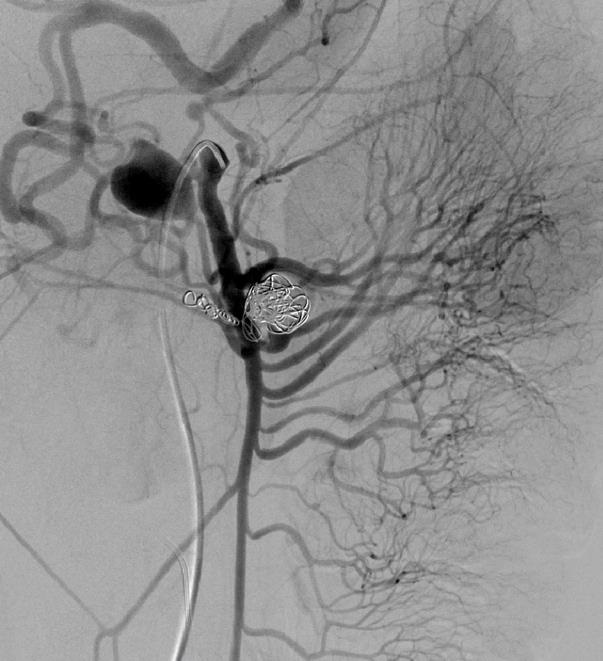

外伤后出血的栓塞

外伤后可见造影剂外溢 |

微导管选择至出血血管 |

出血血管的微弹簧栓子栓塞 |

栓塞后造影 |